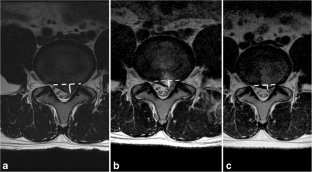

Fig. 2